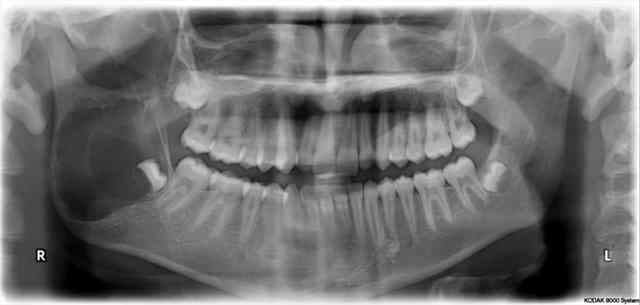

Et là, y'a rien?

15 ans,

Santé RAS

(l'odf a fait une pano il y a 6 mois, n'a rien vu, précédent dentiste en a fait une il y a 2 ans, n'a rien vu non plus,. Conclusion: c'est comme les mensonges: plus c'est gros, plus ça passe...)

Ben je sais pas, mais je poste car le correspondant habituel (un chef de service de sto) parle de résection partielle de la mandibule.

Et comme ça me paraît un peu fort, ben je pose la question, quoi, pour éventuellement orienter ailleurs (vers pus conservateur, quoi).

En plus, si c'est un améloblastome, c'est assez récidivant, non?

Vu la localisation et l'aspect radiologique, cette lésion ressemble à un kératokyste odontogénique. Dans un premier temps ponction pour analyse cytologique.

Quoi qu'il en soit, énucléation complète large en raison du risque de récidive. La marupialisation permettrait de faire diminuer le volume mais dans ce cas là, la mandibule me semble trop touchée pour ne pas subir une hémimandibulectomie.

Lacune de Stafne ?

Ca ne ressemble pas vraiment a un ameloblastome. J'ai eu un cas similaire qui a ete traite par marsupialisation avant d'en faire l'exerese. J'avais posté ce cas la: http://www.eugenol.com/sujets/385313-quand-les-sagesses-ne-sont-pas-sages?page=1#post_427882

Faire une hemimandibulectomie me semble vraiment la dernière chose a faire tant qu'une analyse cytologique n'a pas ete faite.

La question, c'est est-ce que ça va tenir le temps que ça fonctionne (je parle de la marsupialisation)? Parce que le motif de la consult c'est extraction des dds post odf (clairement au second plan maintenant!), qu'il n'a pas mal, mais c'est moi qui flippe pour une fracture subite. Alors qu'une exérèse + fibula immédiate répondrait à la question de solidité.

En même temps, une fracture spontanée est elle si grave par rapport a une mandibulectomie partielle?

Si c'est pas un ameloblastome, c'est quoi? Un KKO récidivant lui aussi? Un kyste folliculaire l'est-il? Je suis un peu nul en patho, c'est vraiment pour ma culture personnelle...

C'est pas un folliculaire, l'aspect radio ne correspond pas. Dans ce cas le germe aurait été refoulé vers la partie postérieure de la mandibule.

un améloblastome ou un KKO oui possible avec une préférence pour l'améloblastome. Mais vu l'aspect assez bien limité, l'âge du patient, ça peut une forme peu agressive de type unikystique. Dans ce cas la virulence est comparable à celle d'un KKO.